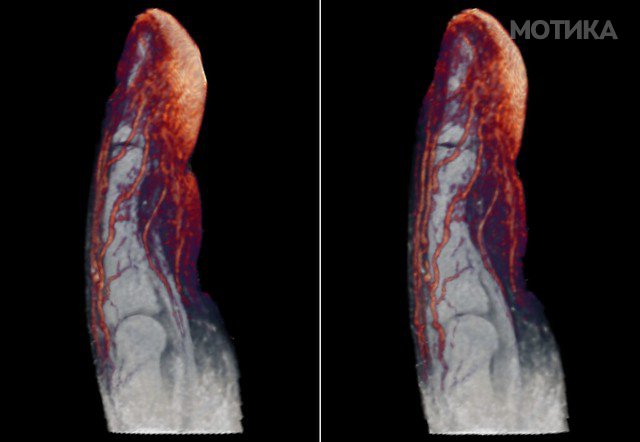

15. Крвни садови на прстот.